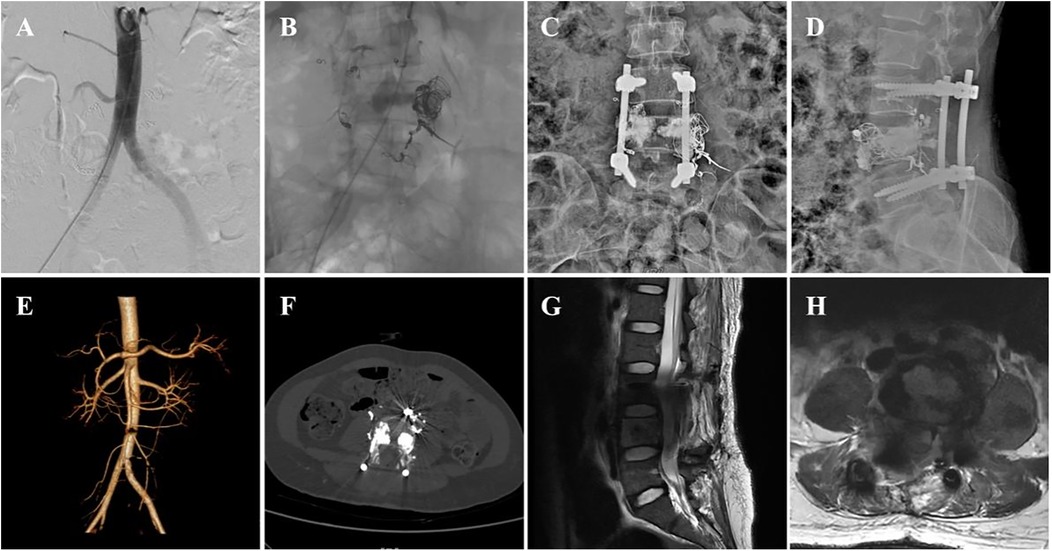

A 37-year-old woman sought treatment from a spinal surgeon because of sudden pain and weakness in both legs and a 6-day history of inability to urinate or defecate. Physical examination revealed decreased strength in the key muscles of both legs: grade II for the iliopsoas, grade II for the quadriceps femoris, and grade I for the tibialis anterior and gastrocnemius. The patient also exhibited reduced sensation in the saddle area. Magnetic resonance imaging (MRI) revealed multiple masses of varying sizes in the L4 vertebra, spinal canal, and surrounding tissues, which appeared as uniformly high signals on T2-weighted images and short TI inversion recovery (STIR) sequences, indicating hemangiomas (Figures 1A–D). The extramedullary subdural hemangioma exhibited “double-eyed” signs and signs of vascular leakage (Figure 1D). Computed tomography angiography (CTA) and digital subtraction angiography (DSA) confirmed an L4 segment arteriovenous fistula with blood supply from the third lumbar artery and a branch of the sacral middle artery (Figures 1E,F), along with intraspinal hemangioma masses (Figure 1H). The patient was diagnosed with aggressive VH and incomplete paraplegia.

Figure 1

Figure 1. Preoperative imaging data of the patient. (A–D) Preoperative MRI images (E), preoperative DSA image, and (F–H) preoperative CTA image.